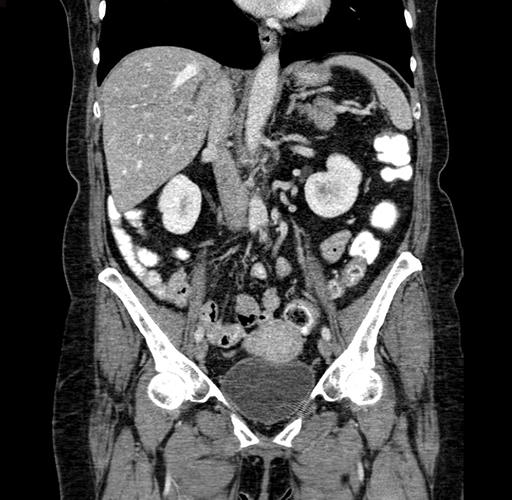

Pre-Chemo: Coronal Venous

Coronal Venous